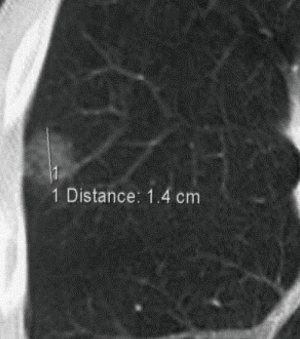

The nodules selected for radio-guided thoracoscopic surgery (RGTS) were those with a diameter <10 mm and/or a distance from the visceral pleura ≥10 mm (e.g., Figure 1). The lesions with a maximum diameter greater than 3 cm and a distance from the pleural surface greater than 4 cm were excluded.